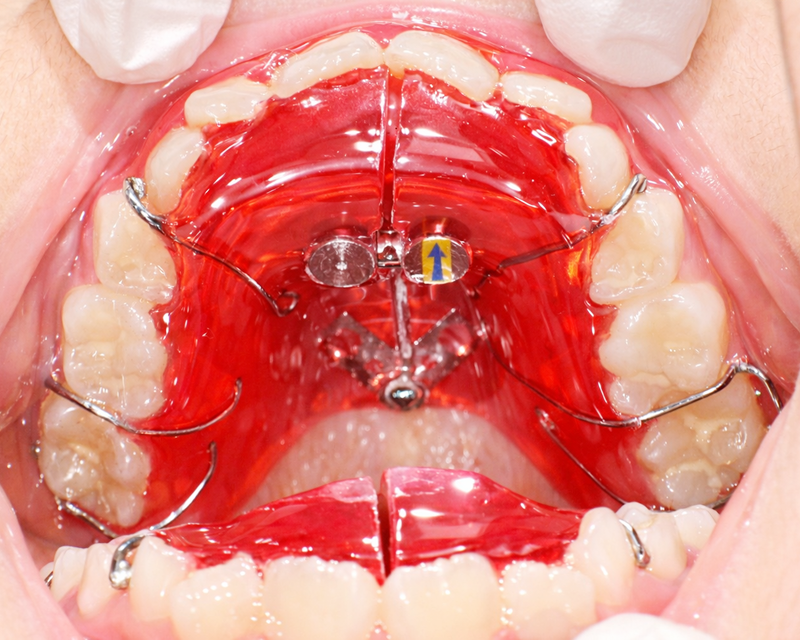

あごを広げて歯が並ぶスペースを作る床矯正

床 (しょう) 装置と呼ばれる取り外し式の装置を使って、あごの幅を少しずつ広げ、永久歯がきれいに並ぶスペースを確保します。乳歯から永久歯に生え変わる時期に効果的です。